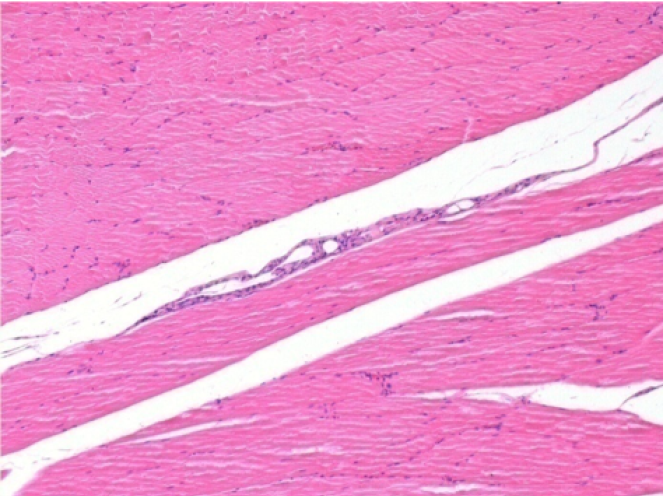

Control

Comment : Nothing to declare after saline solution injection

L:Pretibial-No treatment

R:Pretibial-After 0.1 ml NaCl 0.9% IM